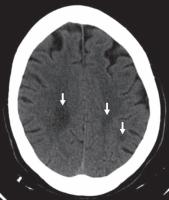

图 6A—淀粉样血管病。未增强 CT 图像识别出以右侧基底神经节为中心的急性出血(星号),提示高血压原因。血肿被血管源性水肿的薄边缘包围并延伸到右额角。两额叶出现慢性脑软化灶(箭头)。

其他微血管病大脑受累的分布不同。在淀粉样血管病中,多灶性和脑叶出血性中风很常见。GRE/磁敏感加权成像可用于检测隐匿性微出血病灶(图6A 、 6B, 和6C)。

2.2出血

血管源性水肿常见于继发于高血压、外伤、凝血病、淀粉样血管病、血管异常、中风和转移瘤的大面积颅内出血附近。据推测,该机制涉及血凝块形成过程中血清蛋白的渗出,导致血肿周围炎症和血脑屏障破坏。水肿在 CT 扫描上表现为周围低密度,在 MR 图像上表现为 T2/FLAIR 高信号。有时,它可能会产生高达原始病变体积两倍的占位效应(图6A , 6B, 和6C)。可以进行医疗管理以降低升高的颅内压。即将发生的脑疝可能需要手术清除和去骨瓣减压术。